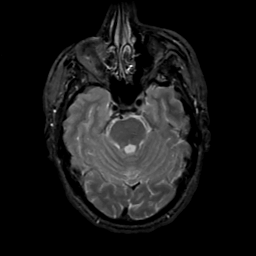

MR Study #15, June 9, 1991 -- Slice #15